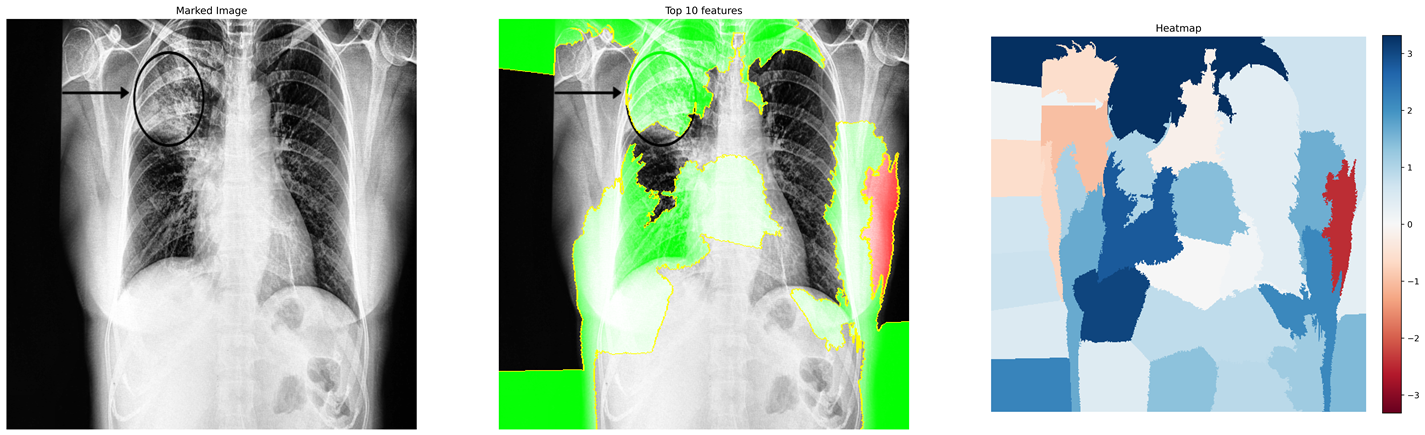

In this work, we only consider the CXR images in a frontal view, namely Poster anterior (PA) and Erect anteroposterior (AP). The first two databases in the above list comprise 520 such images. For the training purpose, we have used these images along with 520 CXR images of normal and pneumonia cases from COVID-19 Radiography Database (Kaggle) COVID19R73:online and Mendeley Chest X-ray Images kermany2018large . Figures 1(a) and 1(b) depicts the manually marked region of interest that distinguishes between COVID-19 and Pneumonia cases in CXR images. The above regions are marked by a radiologist after clinical evaluation of these CXR images.

Figure 8 (a)-(c) shows images relating to COVID-19, Pneumonia, normal cases, respectively. Each subfigure in a row comprises three images of the same patient relating to a medical condition. In each row, the clinical condition has been marked by a radiologist in the first image. In the second image in the same row, the top 10 superpixels obtained using LIME have been marked using green and red colors. Superpixels contributing toward and against the predicted class appear in green and red colors, respectively. Finally, the third image in the same row depicts the LIME-generated heatmap corresponding to the second image. The intensity of the blue color of a particular region in the heatmap corresponds to its relative significance in predicting its class. A radiologist confirmed that in the case of Anteroposterior (AP) chest radiograph (Figure 8(a)), the ill-defined area of ground glass haze in the right lung parenchyma at mid-zone likely represents COVID-19. Similarly, in the Anteroposterior (AP) chest radiograph (Figure 8(b)), the wedge-shaped area of consolidation in the right lung parenchyma at the upper zone likely represents pneumonia. The radiologist confirmed that the regions (though not all) highlighted by LIME correspond to the affected regions in case of both COVID-19 and Pneumonia. This points to the applicability of COV-ELM in the identification of medical conditions such as pneumonia and COVID-19.